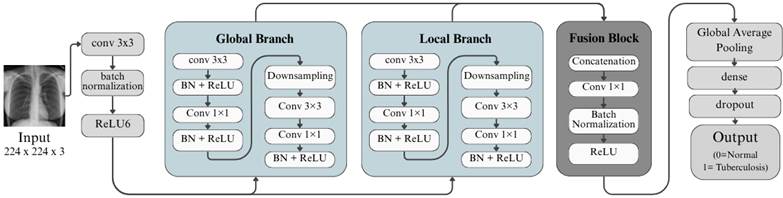

· TBNet

Figura 6. Arquitectura de TBNet.

Elaboración: Los autores.

Finalmente, en la Figura 6 se presenta TBNet, una arquitectura convolucional diseñada específicamente para la detección de tuberculosis en radiografías de tórax, caracterizada por su estructura de dos ramas paralelas.

El modelo inicia con una convolución 3×3 acompañada de normalización por lotes y activación ReLU, encargada de extraer las primeras características de la imagen. A partir de este punto, la red se divide en una rama global, que captura patrones amplios del campo pulmonar mediante bloques convolucionales profundos y operaciones de reducción espacial, y una rama local, que trabaja con convoluciones más ligeras para preservar detalles finos asociados a posibles lesiones tuberculosas.

Posteriormente, ambas ramas se integran en un bloque de fusión mediante concatenación y una convolución 1×1 que combina la información obtenida. La arquitectura continúa con una capa de Global Average Pooling, seguida de una capa densa y Dropout para reducir el sobreajuste, finalizando con una activación sigmoide que permite clasificar las radiografías como normales o con indicios de tuberculosis (Wong et al., 2022).